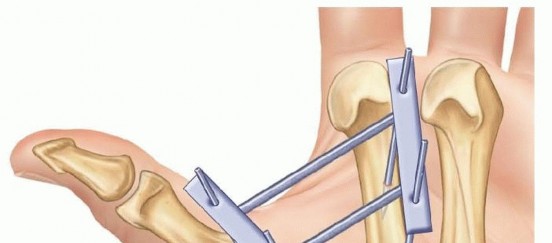

CRPP is the treatment of choice for classic Bennett fractures where the volar-ulnar fragment is too small to reliably accept a lag screw, yet the joint can be anatomically reduced closed. The reduction maneuver is highly specific, designed to counteract the deforming forces of the APL and Adductor Pollicis. Longitudinal traction is applied to the thumb, followed by palmar abduction and pronation. Direct pressure is then applied to the dorsal-radial aspect of the metacarpal base, effectively pushing the shaft back into the anatomic cradle of the intact volar-ulnar fragment.

Once anatomic reduction is confirmed via multi-planar fluoroscopy, percutaneous fixation is achieved. Typically, two 0.045-inch or 0.062-inch Kirschner wires are utilized. The first wire is driven from the dorsal-radial aspect of the metacarpal shaft directly into the trapezium, effectively neutralizing the proximal pull of the APL. A second wire is often placed transversely from the first metacarpal shaft into the second metacarpal to control rotation and maintain the web space. Pins are cut outside the skin and capped to facilitate easy removal in the clinic.